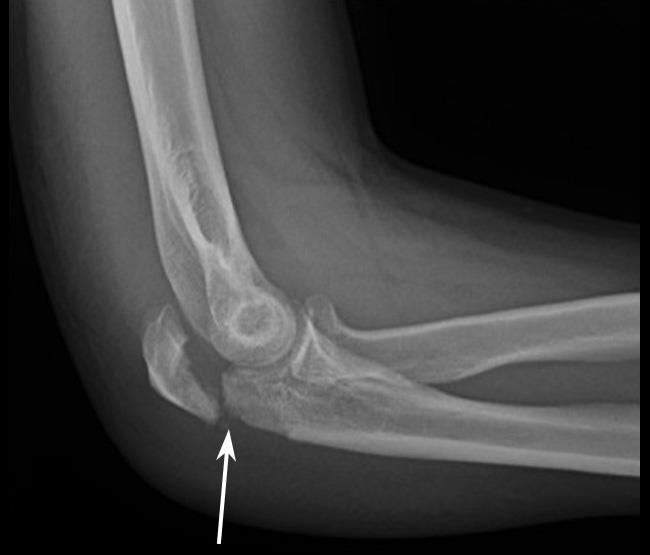

Some undisplaced radial head/neck fractures may not show up on X-ray except for which sign?

Fat pad sign

(usually seen on the lateral X-ray)